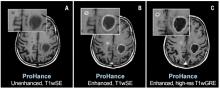

Patients with brain metastases who received whole-brain radiotherapy that avoided memory-specific hippocampal neural stem cells experienced preserved cognitive function, according to results from an NRG Oncology clinical trial. Those patients also reported fewer neurologic symptoms and better cognition over time. The results were presented at the 2019 American Society for Radiation Oncology (ASTRO) Annual Meeting, Sept. 15-18 in Chicago.

ITN Associate Editor Jeff Zagoudis speaks with Vinai Gondi, M.D., co-director of the Brain Tumor Center at the Northwestern Medicine Cancer Center, about the long-term results of a radiation therapy technique called hippocampal avoidance to preserve neurocognitive function for cancer patients with brain metastases at the 2019 American Society for Radiation Oncology (ASTRO) annual meeting.

Watch the VIDEO: Advancements in Radiation Therapy for Brain Cancer and the VIDEO: Multidisciplinary Treatment of Brain Tumors, a previous two-part interview with Gondi.

Read the article "Hippocampal Avoidance Using IMRT Now Recommended as Standard of Care for Brain Metastases"